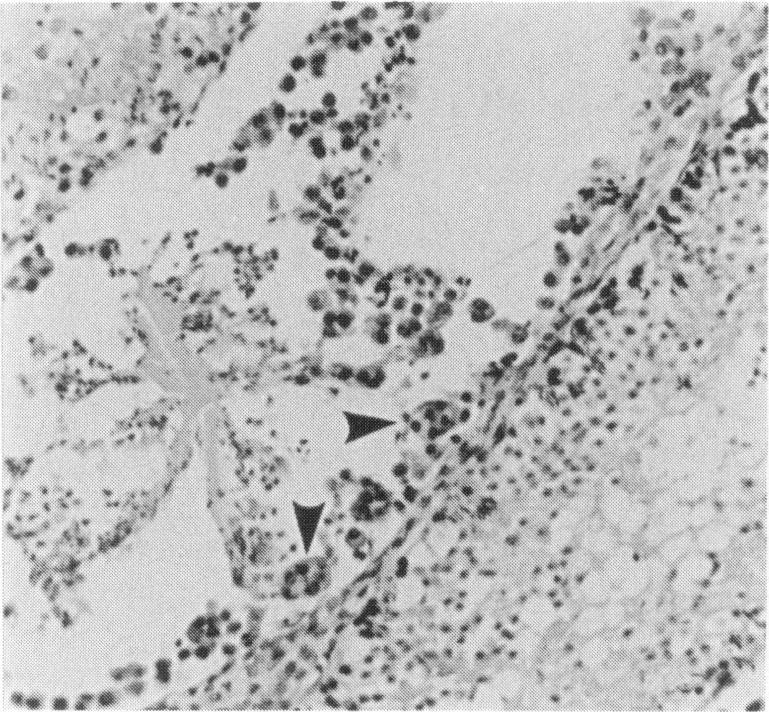

Testes of 8-week-old male Syrian hamsters which were inoculated intraperitoneally with 10(5) plaque-forming units of the D variant of encephalomyocarditis virus (EMC-D) were examined virologically and histologically. Viral replication was detected from 1 day post inoculation (1 DPI), became more prominent 3 DPI, and was no longer demonstrated 7 DPI. The weight of testis decreased in course of time and it was about 2% of that of control 6 weeks post inoculation (6 WPI). Histopathologically, degeneration and/or necrosis of germinal cells and spermatogonia were observed in many seminiferous tubules of all hamsters 3 DPI. At 7 DPI, luminal obstruction by cellular debris and subsequent replacement of them by mesenchymal cells were common in mildly atrophic tubules surrounded with inflammatory cells. Thereafter, atrophy of seminiferous tubules became severer with the lapse of time and, in addition to plasma cell infiltration, apparent increase in the number of Leydig cells was found in the interstices. No regenerative signs of germinal epithelia were detected by 6 WPI. This is the first report of EMC virus-induced orchitis.

对8周龄雄性叙利亚仓鼠的睾丸进行了病毒学和组织学检查,这些仓鼠经腹腔接种了10⁵ 个脑心肌炎病毒D变种(EMC-D)的蚀斑形成单位。接种后1天(1 DPI)检测到病毒复制,3 DPI时更为显著,7 DPI时不再检测到。随着时间推移,睾丸重量下降,接种后6周(6 WPI)时约为对照组的2%。组织病理学上,3 DPI时,所有仓鼠的许多生精小管中均观察到生殖细胞和精原细胞的变性和/或坏死。7 DPI时,轻度萎缩的小管内常见细胞碎片造成的管腔阻塞,随后这些碎片被间充质细胞取代,周围有炎症细胞。此后,随着时间推移,生精小管萎缩变得更加严重,除浆细胞浸润外,间质中Leydig细胞数量明显增加。6 WPI时未检测到生精上皮的再生迹象。这是关于EMC病毒诱导睾丸炎的首次报告。